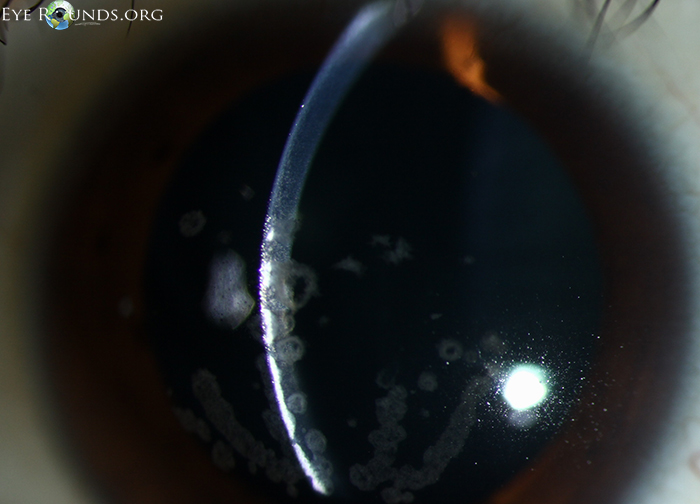

각막의 기질에 빵부스러기, breadcrumb 모양의 흰색의 침착물이 쌓이는데,

이는 각막의 중심부, 기질의 앞쪽쯕에 모이게됩니다.

혼탁의 모양은 둥글며, 병변들의 윤곽이 명확하며

흔히 눈송이, 빵부스러기 등의 모양으로 하고 있으며, 경계가 명확하여,

병변이 없는 부위과 구분됩니다.

단, 아무리 주변부로 퍼지더라도 윤부 2-3mm는 혼탁이 발생하지 않습니다.